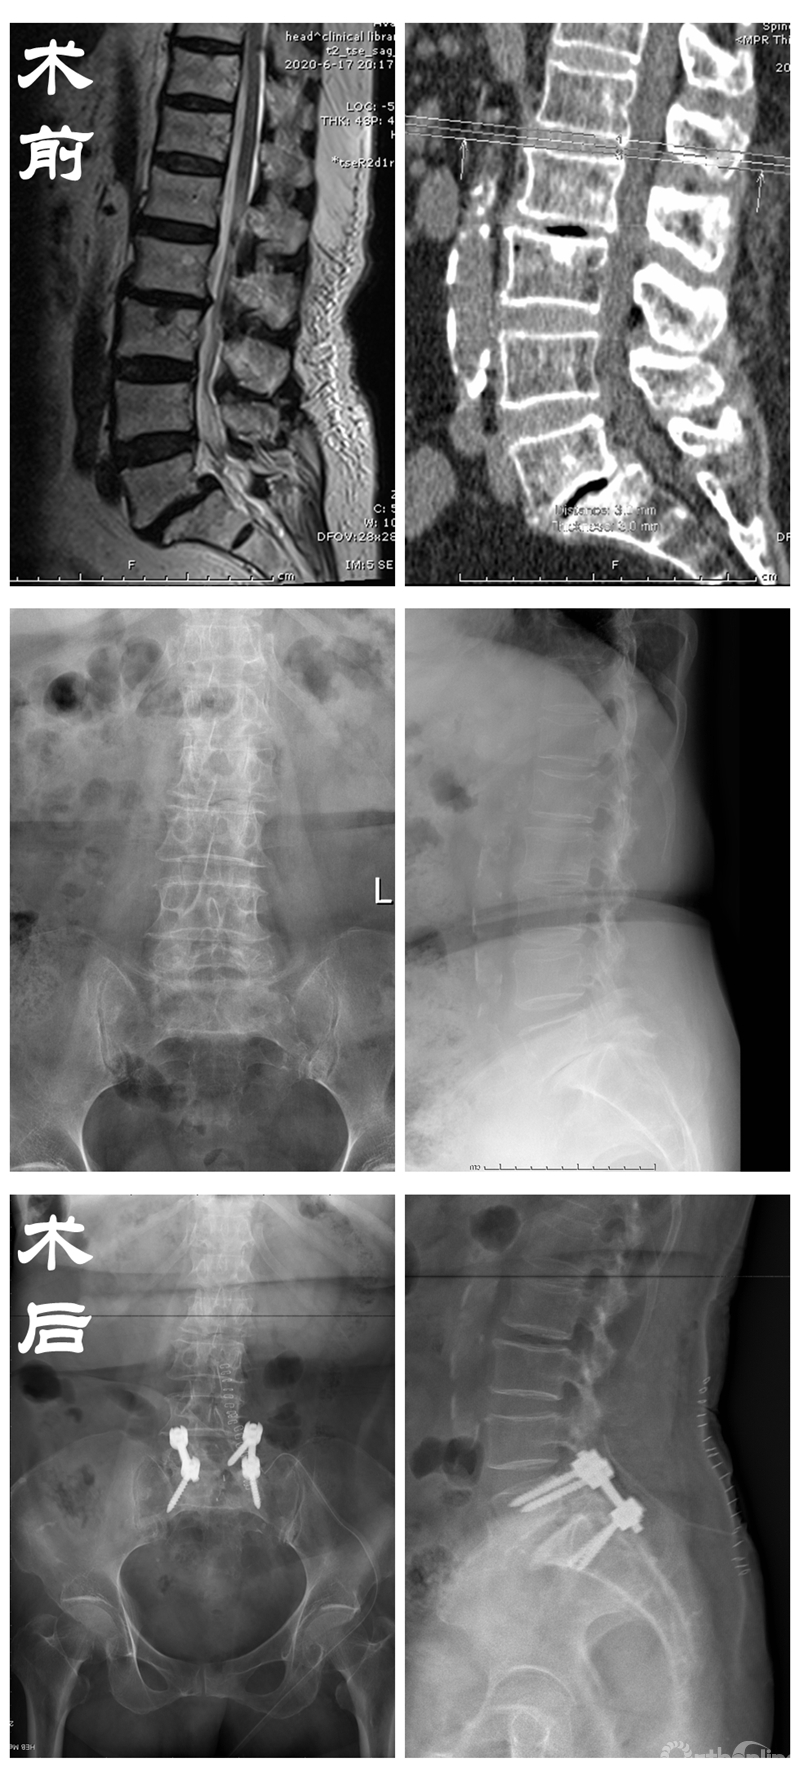

医疗技术的发展也为老龄化社会带来了翻天覆地的变化。85岁王奶奶患有的腰椎滑脱症多年,常常因此痛不欲生。众所周知,对于80岁以上的高龄患者进行手术本身风险就很高,医生的原则是能保守就不开刀。

在备受折磨的患者苦苦央求下,丁文元教授为解决患者病痛,立即召集多科室进行会诊,在确认患者的心、肺、脑功能可以负担手术及麻醉后,为患者进行了腰椎切开复位固定融合术,术后患者腰腿疼缓解,日常活动均可自理。

患者资料